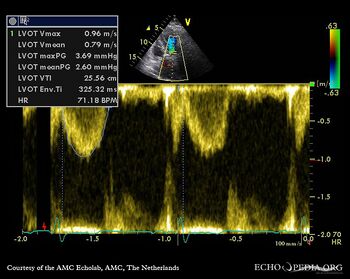

Aortic valve stenosis

J. Vleugels, AMC, The Netherlands